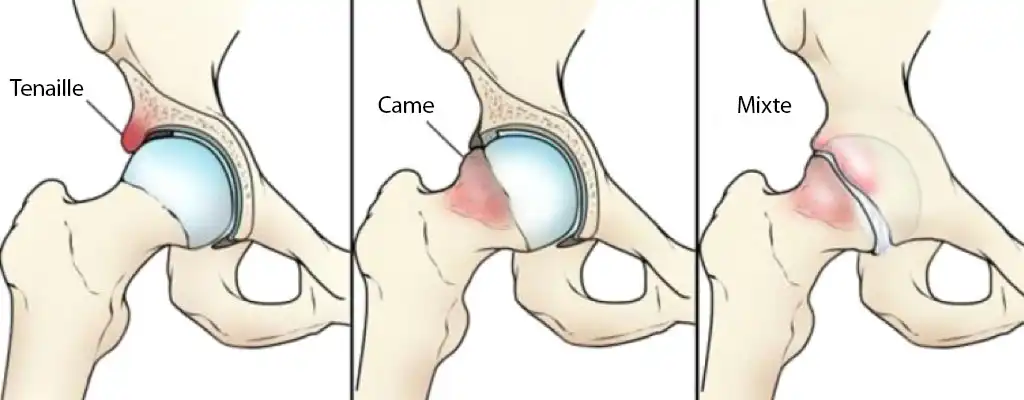

Anomalie morphologique de la tête fémorale (type came) ou du rebord acétabulaire (type pince) générant un accrochage mécanique douloureux, source de lésions cartilagineuses et labrales.

Ostéoplastie